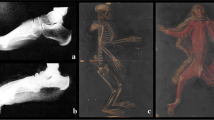

a In this specimen a calcaneal osteotomy (CO) was performed whereby an osteotomy angle was used of approximately 45° relative to the foot sole. A anterior calcaneal fragment, B posterior calcaneal fragment. b After performing a CO the foot was dissected. The plantar apeunorosis (PA) and Achilles tendon (AT) insert on the posterior calcaneal fragment. Both structures carry forces during gait and may cause shear forces on the posterior calcaneal fragment

The locations of the insertions of the plantar aponeurosis (PA) and the Achilles tendon (AT) on the posterior calcaneal fragment were identified after a regular osteotomy (Fig. 1a). Five cadaver feet were dissected after performing a CO in 45° relative to the plantar surface of the foot sole (Fig. 1a). In all specimens the PA and the AT were inserted on the posterior calcaneal fragment (Fig. 1b). On the anterior calcaneal fragment, the long plantar ligament (PL) was inserted.